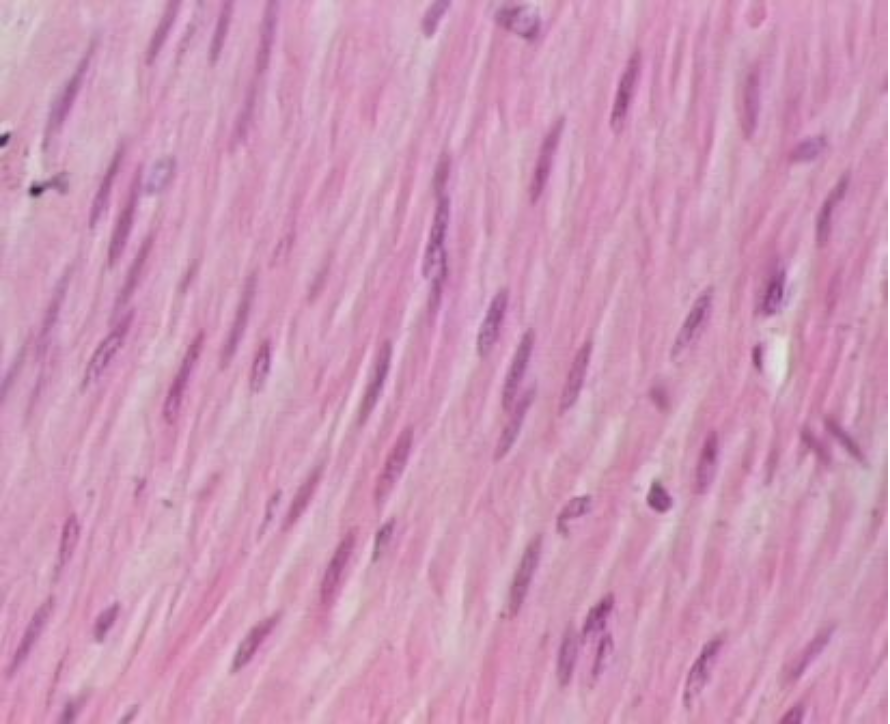

Smooth Muscle